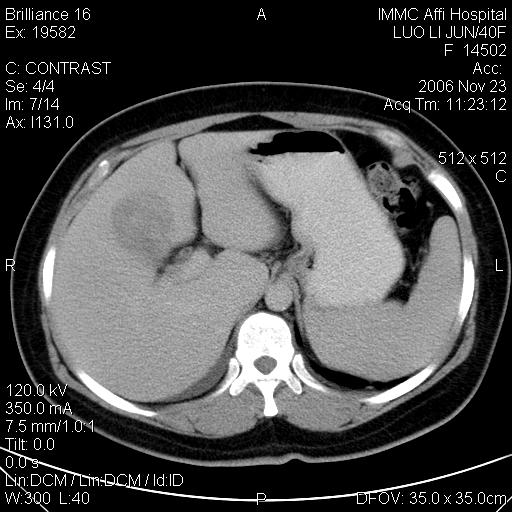

标题: CT5664:我也发一个肝脏的片子大家看看

很典型的肝癌。

速升速降,典型肝癌.

是啊,典型的早出早归!

快进快出典型肝癌.

符合肝癌的增强特征。支持肝癌!

病灶好圆!可能恶性度不高。

不能除外肝细胞腺瘤吧,还是得结合病史。

很好的片子,可惜增强做的比较失败,a期时间没有把我好,实际到了静脉早期了,否则会更典型。

最终考虑是肝腺瘤